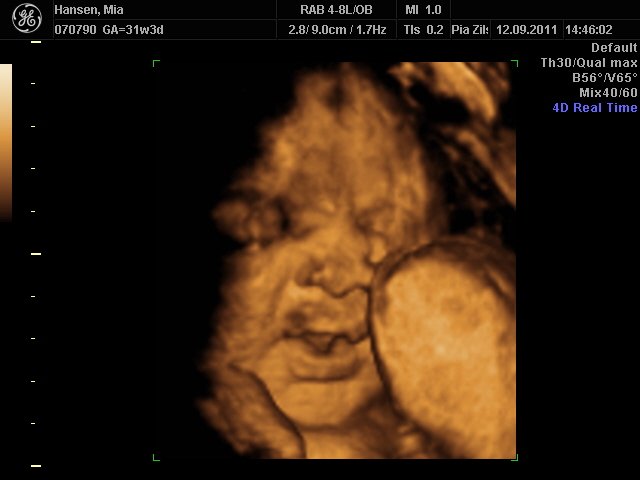

Så er vi næsten lige kommet hjem fra scanningen i københavn

Hold da helt op hvor hun kunne charme sin mor & far, hun er bare så lækker, hun lå lige som hun skulle for at få gode billeder af hende

Hun er stadigvæk en rigtig putterøv, men vi fik en masse smil og trut-munde af hende

hun har lange øjenvipper og hår i nakken

Mia 31+3